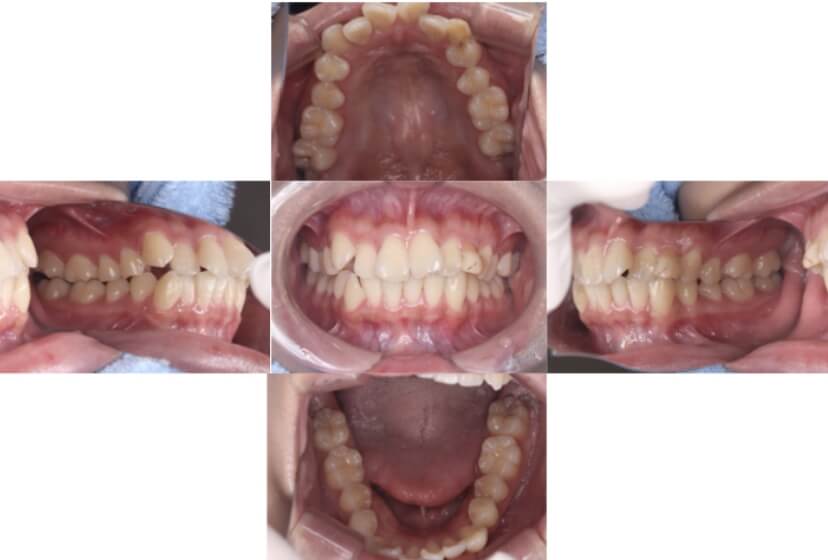

症例1

上顎前突、叢生

抜歯

ブラケット矯正

上下顎叢生、上顎前突(出っ歯、上下の前歯のガタガタ)のケースです。

装置はラビアル(上下表側)で、上顎の小臼歯を2本抜歯を行っています。抜歯したスペースを使って、上の前歯の後方移動と叢生(ガタガタ)と出っ歯の改善を行っています。下は歯と歯の間にIPR(隣接面削合)を行い、スペースを確保し、叢生の改善を行っています。

主訴 前歯のガタガタと出っ歯が気になる。

年齢・性別 47歳 女性

お住まいの地域 神奈川県川崎市

治療方針 抜歯スペースおよびIPRを利用して上前歯の叢生(ガタガタ)の改善

抜歯部位 上顎左右第一小臼歯

使用装置 ラビアル(上下表側)、顎間ゴム

治療期間 2年0か月

治療回数 15回

リテーナー クリアリテーナー

BEFORE

AFTER